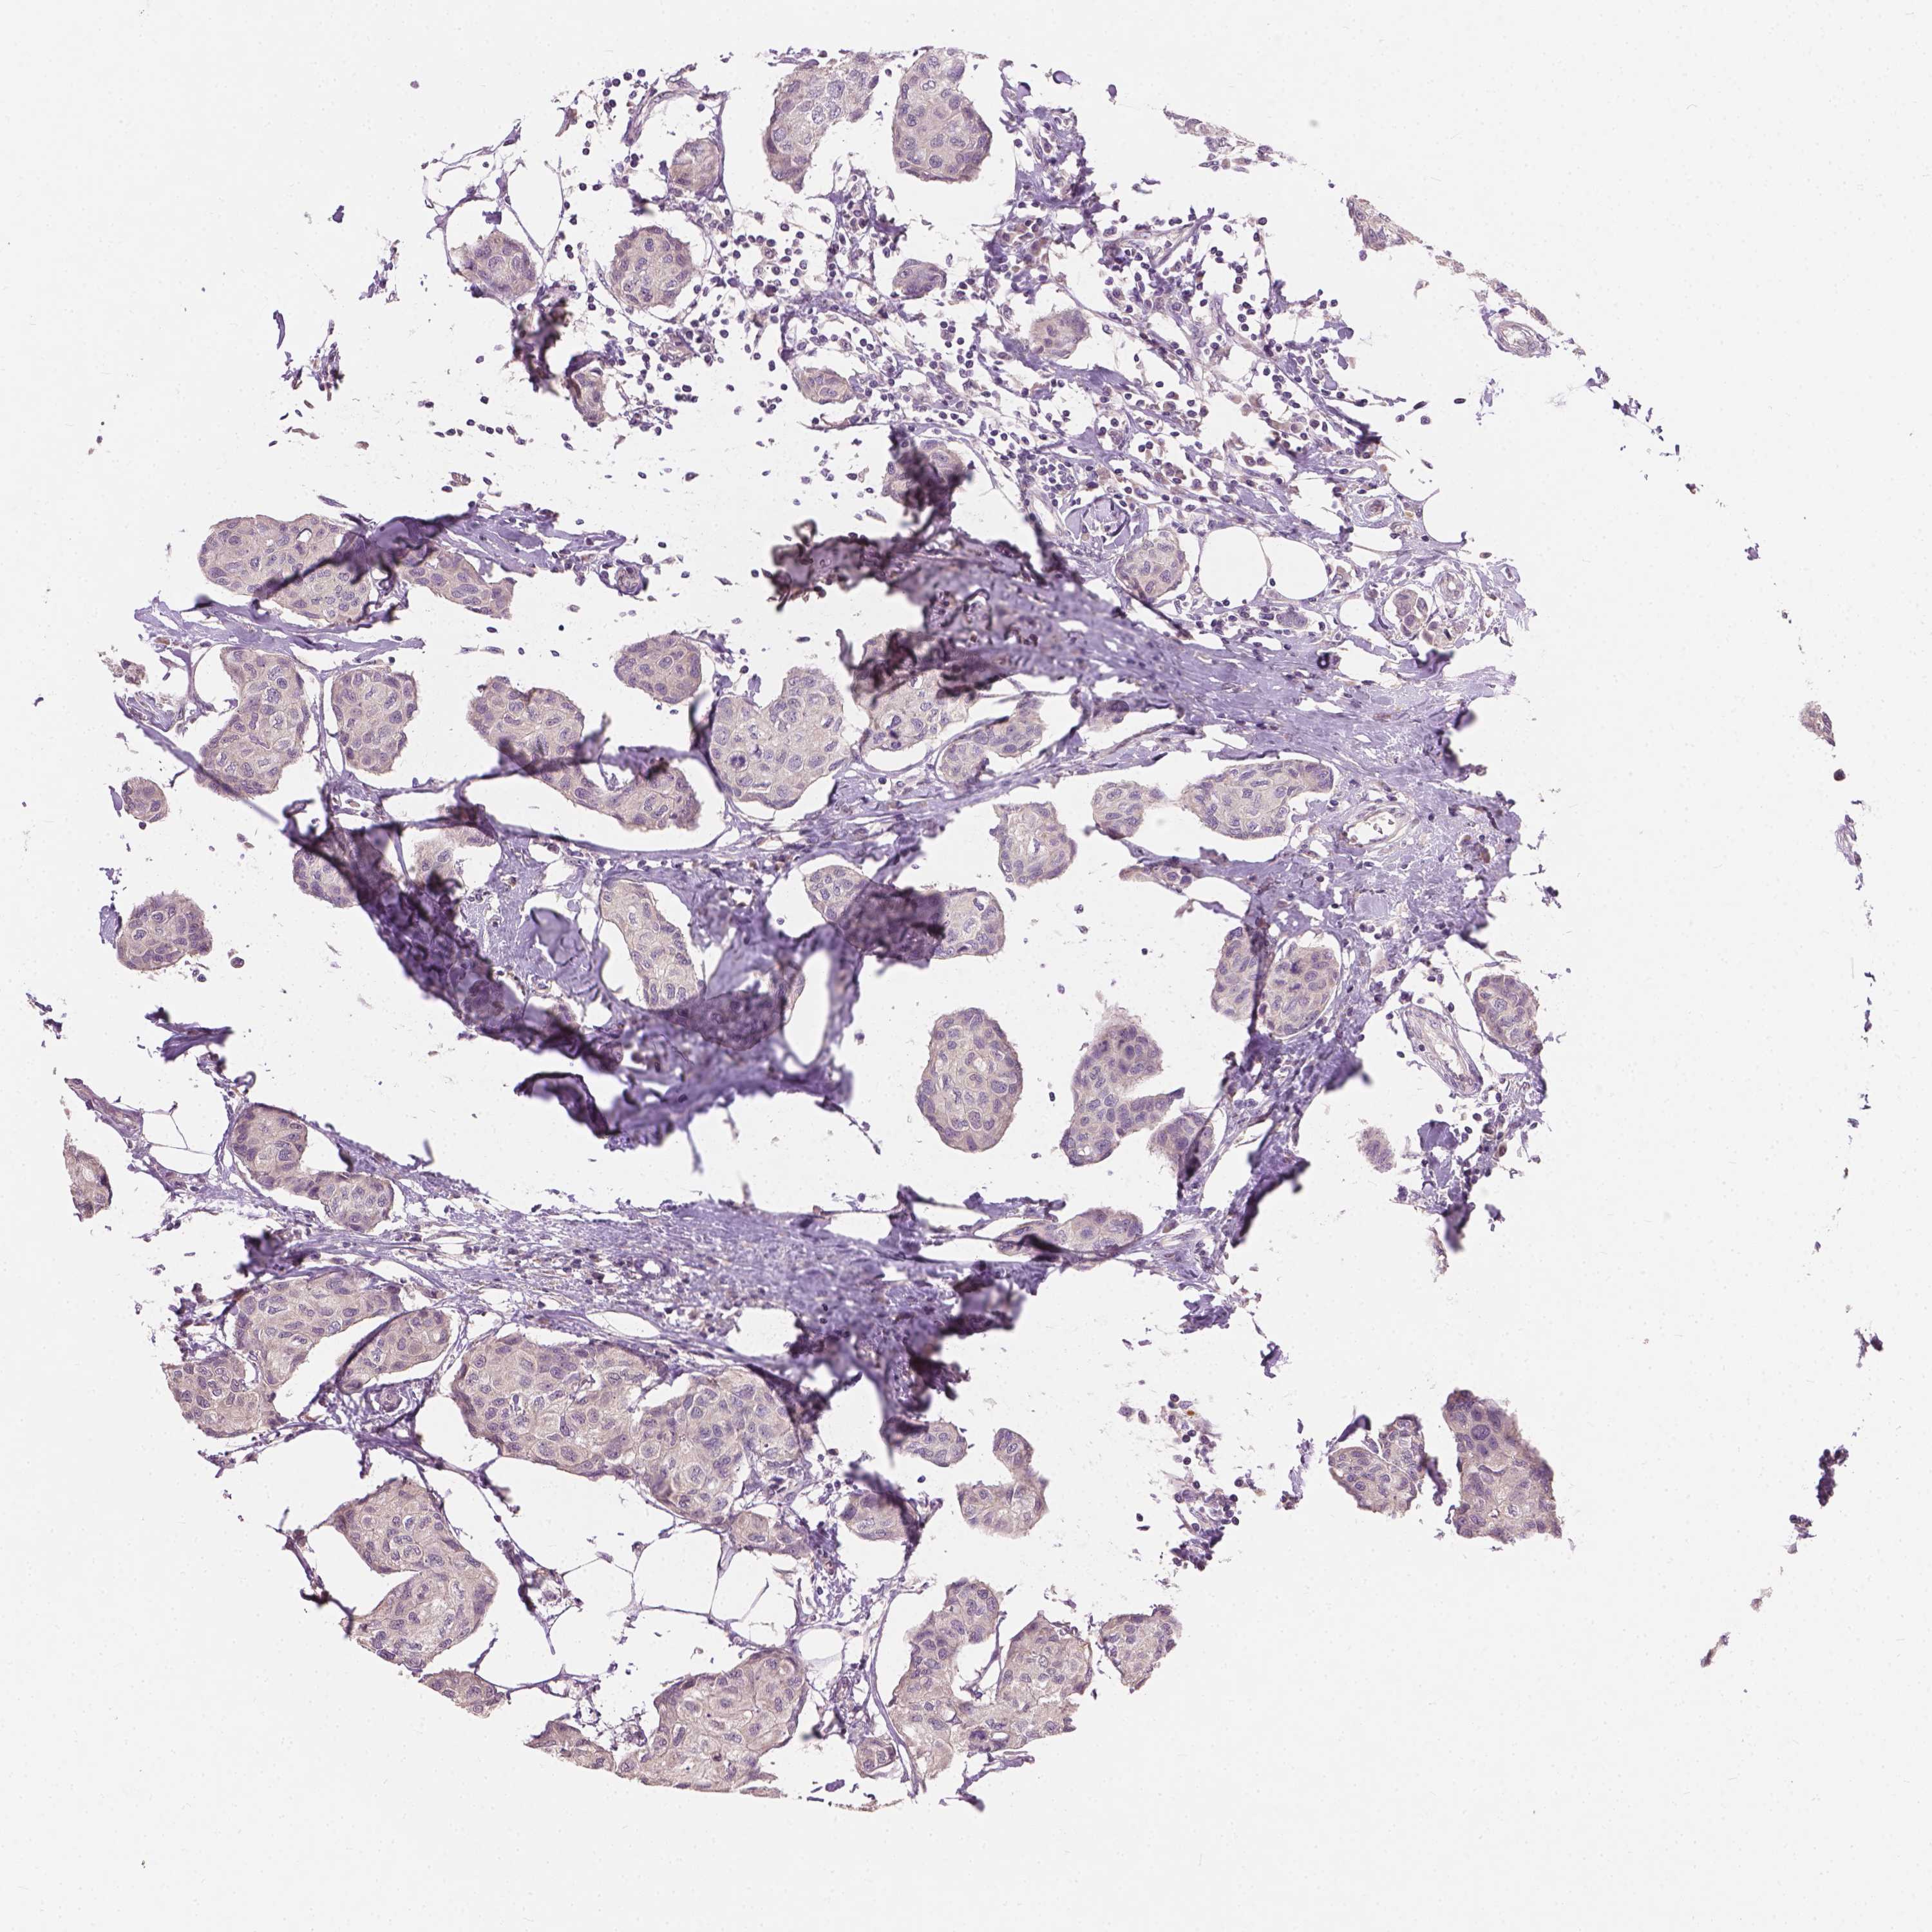

CANCER BREAST CANCER Show tissue menu

BRCA TCGA BRCA VALIDATION PROTEIN EXPRESSION

ANTIBODIES

AND

VALIDATION